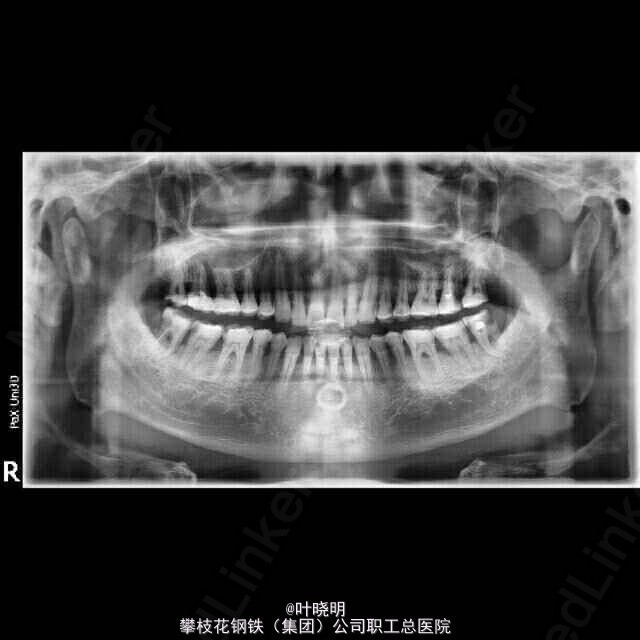

左下8根管治疗

38颊面深龋,探已穿髓,松(-),冷测敏感并持续数秒,叩(+-):有对合且关系良好。

诊断:38慢性牙髓炎急性发作 治疗:初诊局麻下扩穿髓孔,备洞置“三甲”失活剂,半月复诊去冠髓,摄根尖片见近中根弯曲向远中,拔髓封“CP”一W;复诊时先用不锈钢1O号K锉(21mm)预弯达根尖止点;再用S3镍钛锉配合EDTA对根管进行充分润滑;轻微施压使S3锉沿着根管走向向根尖推进,反复冲洗再封“Ca(OH)2” 一次,复诊时试尖根充并恒垫充填。